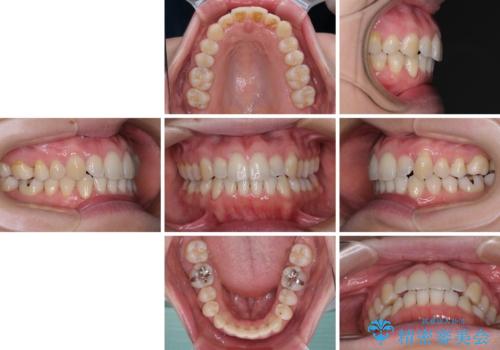

- 受け口傾向でクロスバイトの前歯を治したいとのことで来院された患者様です。

下顎骨が若干左側に変位していたため、右側にアンカースクリューを使用し、積極的に移動させながらインビザラインにて矯正治療を行うこととしました。

インビザラインによる矯正治療は、受け口傾向の治療に非常に適した方法であり、事前にシミュレーションに沿って治療を進めることできます。

今回の治療では骨格的な偏位があったためアンカースクリューを使用し、より確率の高い治療を行うことができました。